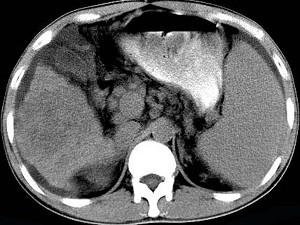

问题 男,35岁,有乙肝病史多年,AFP阳性,影像检查如图,最可能的诊断是 ( )

选项 A.肝硬化腹水 B.肝血管 C.肝脓肿 D.肝癌、硬化腹水 E.肝硬化,结节性增生

答案 D